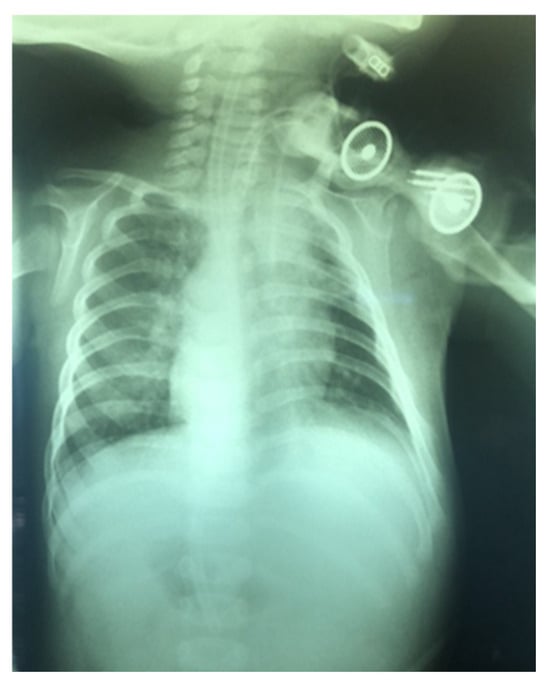

- A midline incision is made on the neck, halfway between the cricoid cartilage and the jugular notch (Figure 1). The incision can be either horizontal or vertical, with a horizontal incision being used in most cases.